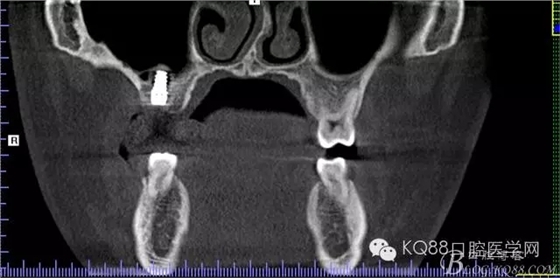

下面是拔牙前 CBCT

清晰可見根尖部陰影區(qū)域明顯。遠(yuǎn)中頰根

近中頰跟,同時(shí)可以看出離上頜竇比較近,且伴有骨缺損。

這個(gè)切面可以看到根裂。